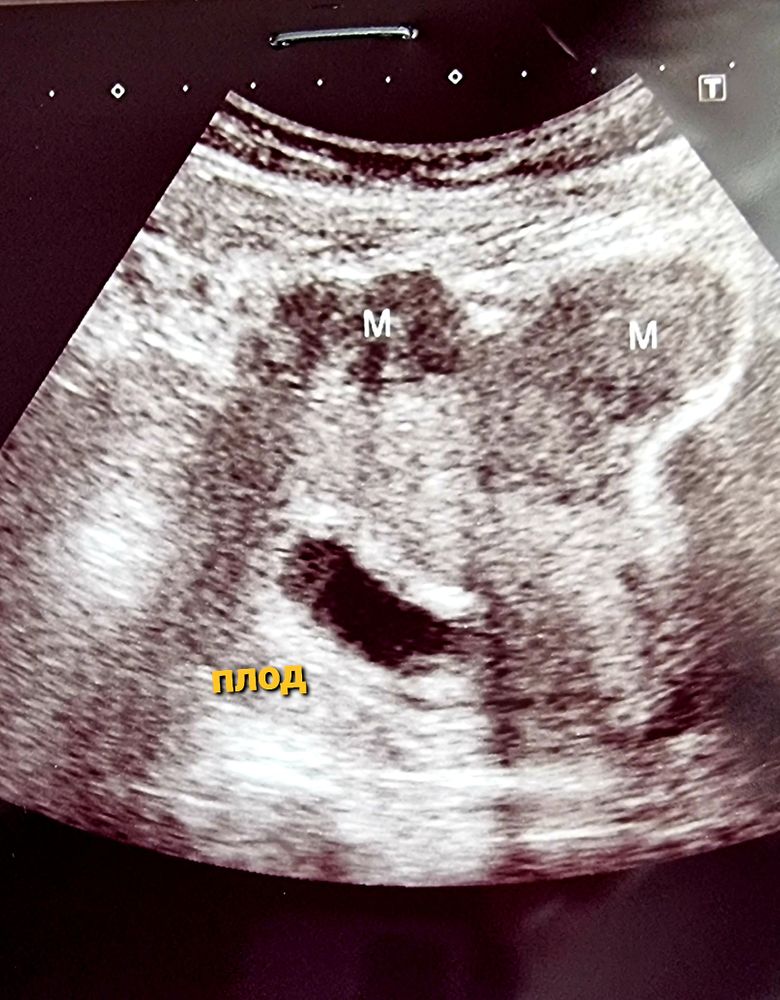

8-9 нед Б и МИОМА

У меня их штуки 4,все по передней стенке, на первом скрининге врач сказал ни кто не скажет как они себя поведут, но прикрепление у меня по задней стенке, и что малышу ничего не мешает, и так всё хорошо